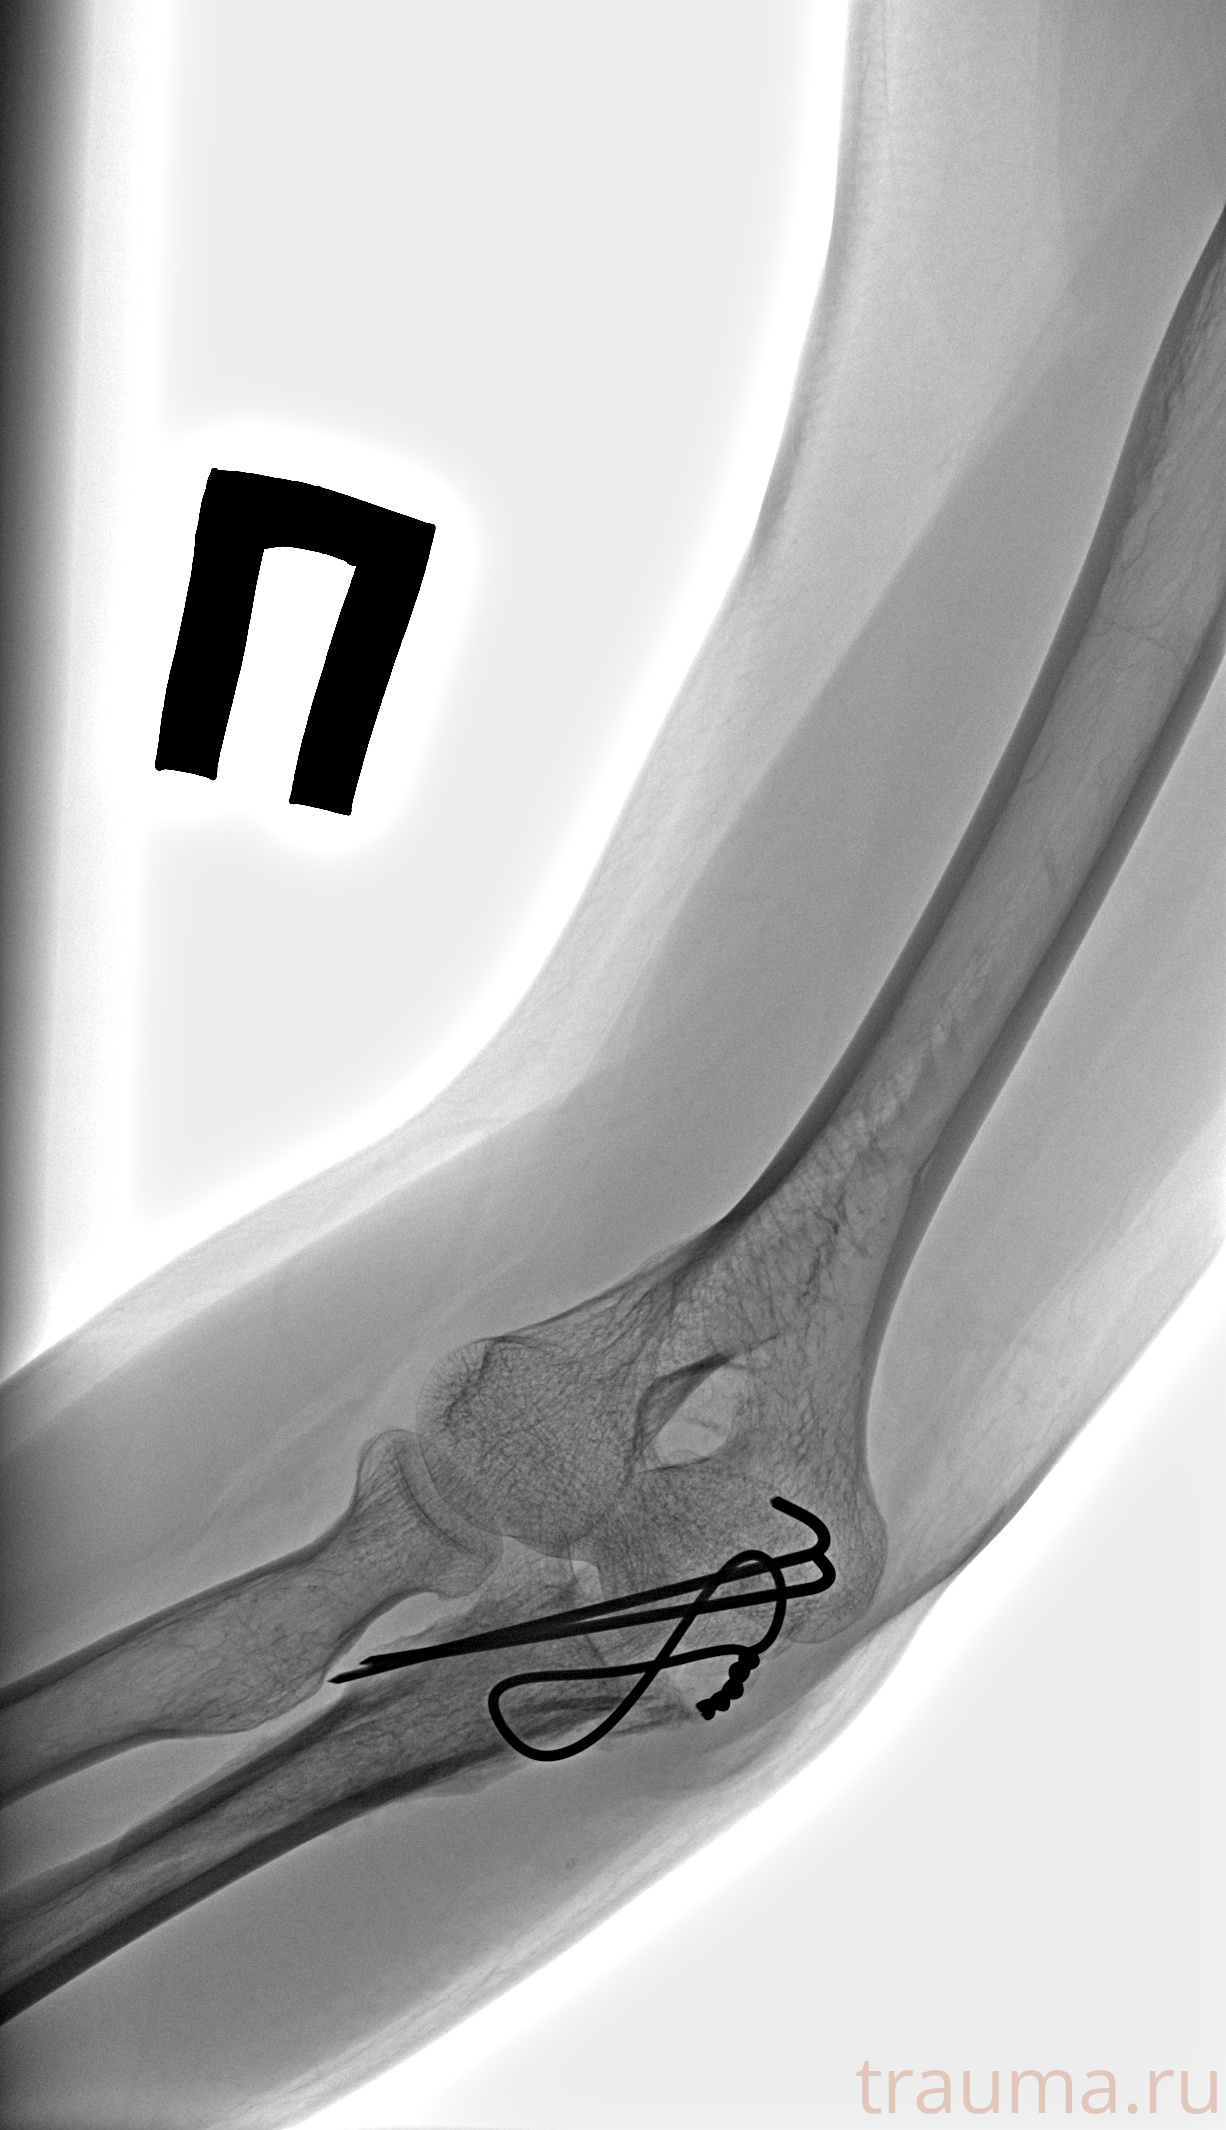

Рентген на дому: по вашему адресу приезжает врач-рентгенолог, травматолог-ортопед с мобильным рентгеновским аппаратом, проводит диагностику травмы или заболевания, делает необходимые рентгенограммы, дает рекомендации по дальнейшему лечению. Получить качественные снимки в домашних условиях возможно благодаря уникальной методике, разработанной МосРентген Центром для института  Склифосовского